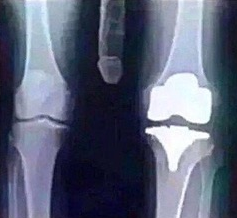

Vous êtes ici : Accueil > Photos humour > J'ai dû être opéré du genou. Le cartilage avait pratiquement disparu.

J'ai dû être opéré du genou. Le cartilage avait pratiquement disparu.

Mon cas devait être assez inhabituel parce que toutes les infirmières venaient voir mes radios.!!!